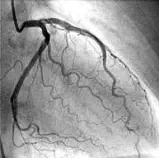

Коронарографија

Коронарографијата е инвазивна дијагностичка процедура за проценка на состојбата

на коронарните артерии, кои го снабдуваат срцето со крв. Се изведува со

воведување катетер преку артерија (обично во рака или препона) до срцевите

артерии, каде се вбризгува контрастно средство за да се визуелизираат на рендген.

Ова овозможува откривање на стеснувања, блокади или аномалии во артериите,

кои можат да предизвикаат срцев удар или ангина. Постапката трае околу 30-60

минути, под локална анестезија, со минимален ризик од компликации.

Коронарографијата е златен стандард за дијагноза на коронарна артериска болест

и помага во планирањето на понатамошниот третман, како ангиопластика или

бајпас.